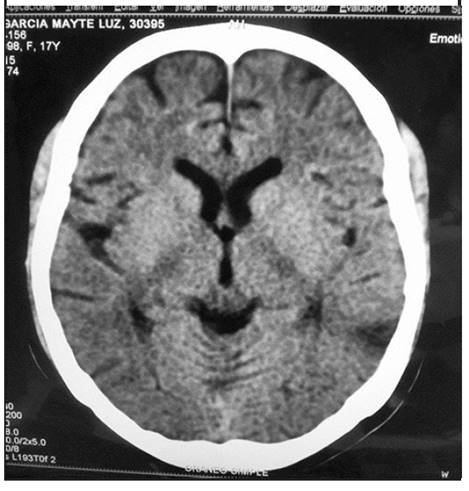

El día 12 continúa con MAT activa y severo compromiso neurológico, encefalopática y presenta, adicionalmente, episodio de convulsión por lo que se realiza TAC de cráneo (figura 2), evidenciando: zona isquémica temporal izquierda. Nuevamente es valorada por ginecología, quienes realizan junta médica descartando procesos infecciosos relacionados y continúa manejo expectante en UCI. Se reciben paraclínicos adicionales para abordajes diferenciales de MAT sistémicas con reporte de actividad de ADAMTS 13: 64%; pruebas de complemento: C3: 73,4mg/dl (90-180mg/dl); C4: 8.6 mg/dl (10-40mg/ dl),ambas disminuidas, sin evidencia de enfermedad autoinmune concomitante. Se considera cuadro de MAT asociada al embarazo, con evolución tórpida pese a manejo del síndrome HELLP como primera aproximación diagnóstica, con resultado de ADAMTS13 que descarta la presencia de PTT asociado a la gestación y se considera el diagnóstico de SHUa como el diagnóstico definitivo, que explica la persistencia del severo compromiso sistémico, la MAT persistente, la HTA de difícil manejo que requiere polifarmacia y el compromiso multisistémico actual, por lo que se decide iniciar plasmaféresis, en espera de disponibilidad de tratamiento dirigido a bloquear el complemento. Se ordena vacunación previa contra meningococo. La paciente continúa encefalopática, en estatus convulsivo, manejada con ácido valproico, sedación con benzodiacepinas y Propofol, sangrado espontáneo por tubo orotraqueal.